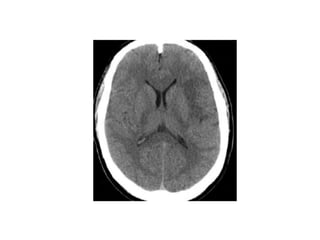

Hypertensive encephalopathy

-This condition is related to cerebral edema and

charactarized by headache ,nausea,and vomiting

followed by nonlocalizing symptoms such as

restlessness ,confusion ,seizures ,and coma.

-Although these insidious neurologic symptoms

differ from abrupt onset of focal neurologic

symptoms typically seen with a stroke or

hemorrhage an MRI should be obtained to

exclude stroke or hemorrhage

Magnetic resonance imaging

may reveal edema of the white

matter of the parieto-occipital

regions a finding termed :

reversible posterior

leukoencephalopathy

Hypertensive encephalopathy -This conditionis related to cerebral edema and charactarized by headache ,nausea,and vomiting followed by nonlocalizing symptoms such as restlessness ,confusion ,seizures ,and coma. -Although these insidious neurologic symptoms differ from abrupt onset of focal neurologic symptoms typically seen with a stroke or hemorrhage an MRI should be obtained to exclude stroke or hemorrhage

Magnetic resonance imaging mayreveal edema of the white matter of the parieto-occipital regions a finding termed : reversible posterior leukoencephalopathy